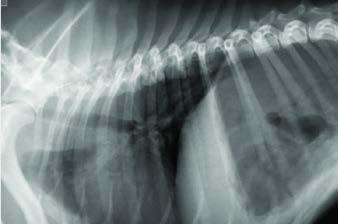

Se realiza radiografía de tórax (Fig. 1) que revela car-

diomegalia generalizada severa, índice de Buchanan de 15 cuerpos vertebrales, que puede corresponder a un severo aumento de las cámaras cardiacas, o a la presencia de líquido pericárdico. Se observa, además, un patrón pulmonar intersticial perihiliar, compatible con edema pulmonar, foco de neumonía o hemorragia pulmonar.

M. López,1 V. Fernández,2 J. Engel3 1Servicio de cardiología y diagnóstico por imagen. 2Servicio de cirugía. Laclinicaveterinaria. c/Marroquina 26. 28030 Madrid. 3Servicio de cardiología. ANICURA-Benipeixcar Hospital Veterinario. Avinguda de la Constitució 68, bajo izq. 46009 Valencia. ANICURA-San Francisco Hospital Veterinario. c/ Sant Francesc 65. 12500 Vinaròs (Castelló). ANICURA-San Vicente Hospital Veterinario. c/ Veterinario Manuel Isidro Rodríguez García 17. 03690 San Vicente del Raspeig (Alicante). Figura 1. Radiografía lateral de tórax en la que se observa cardiomegalia generalizada, VHS 15. Patrón alveolar intersticial compatible con edema pulmonar. Patrón vascular mixto y patrón bronquial en lóbulos caudales, compatible con bronquitis crónica, mineralización por degeneración senil.

En el caso que presentamos podemos confirmar cardiomegalia severa y edema pulmonar dado que el estudio radiológico del tórax permite establecer el tamaño cardiaco y valorar el patrón pulmonar. La insuficiencia cardíaca congestiva izquierda se caracteriza por un patrón intersticial, que puede evolucionar a patrón alveolar en la región perihiliar que tiende a distribuirse hacia caudodorsal, característico del edema pulmonar cardiogénico, patrón vascular venoso.